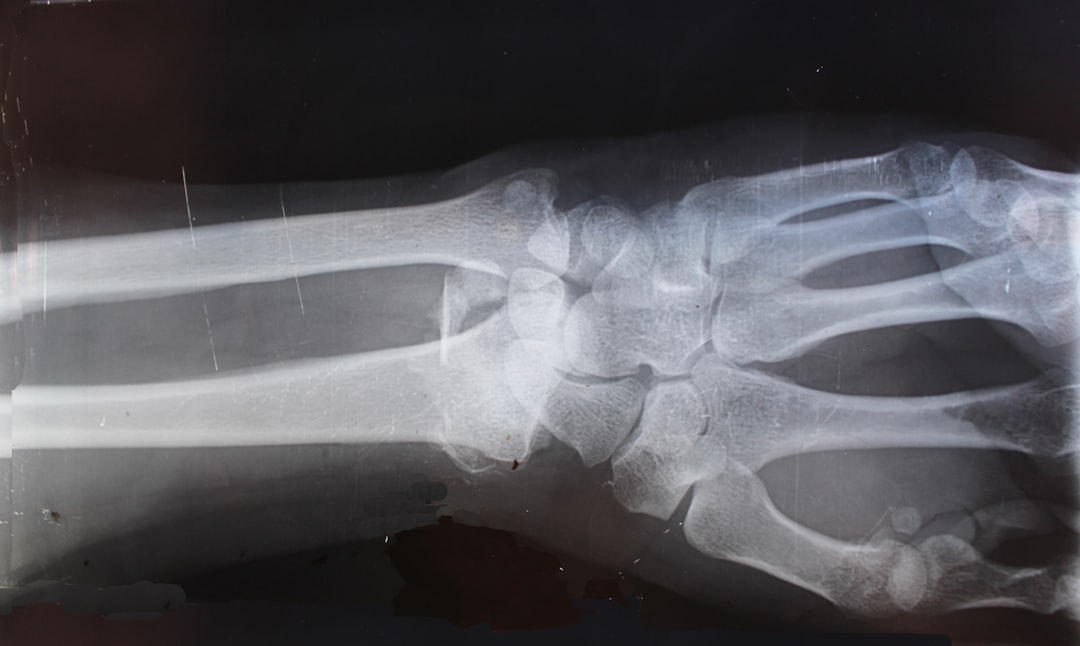

• Imaging studies such as X-rays or MRI